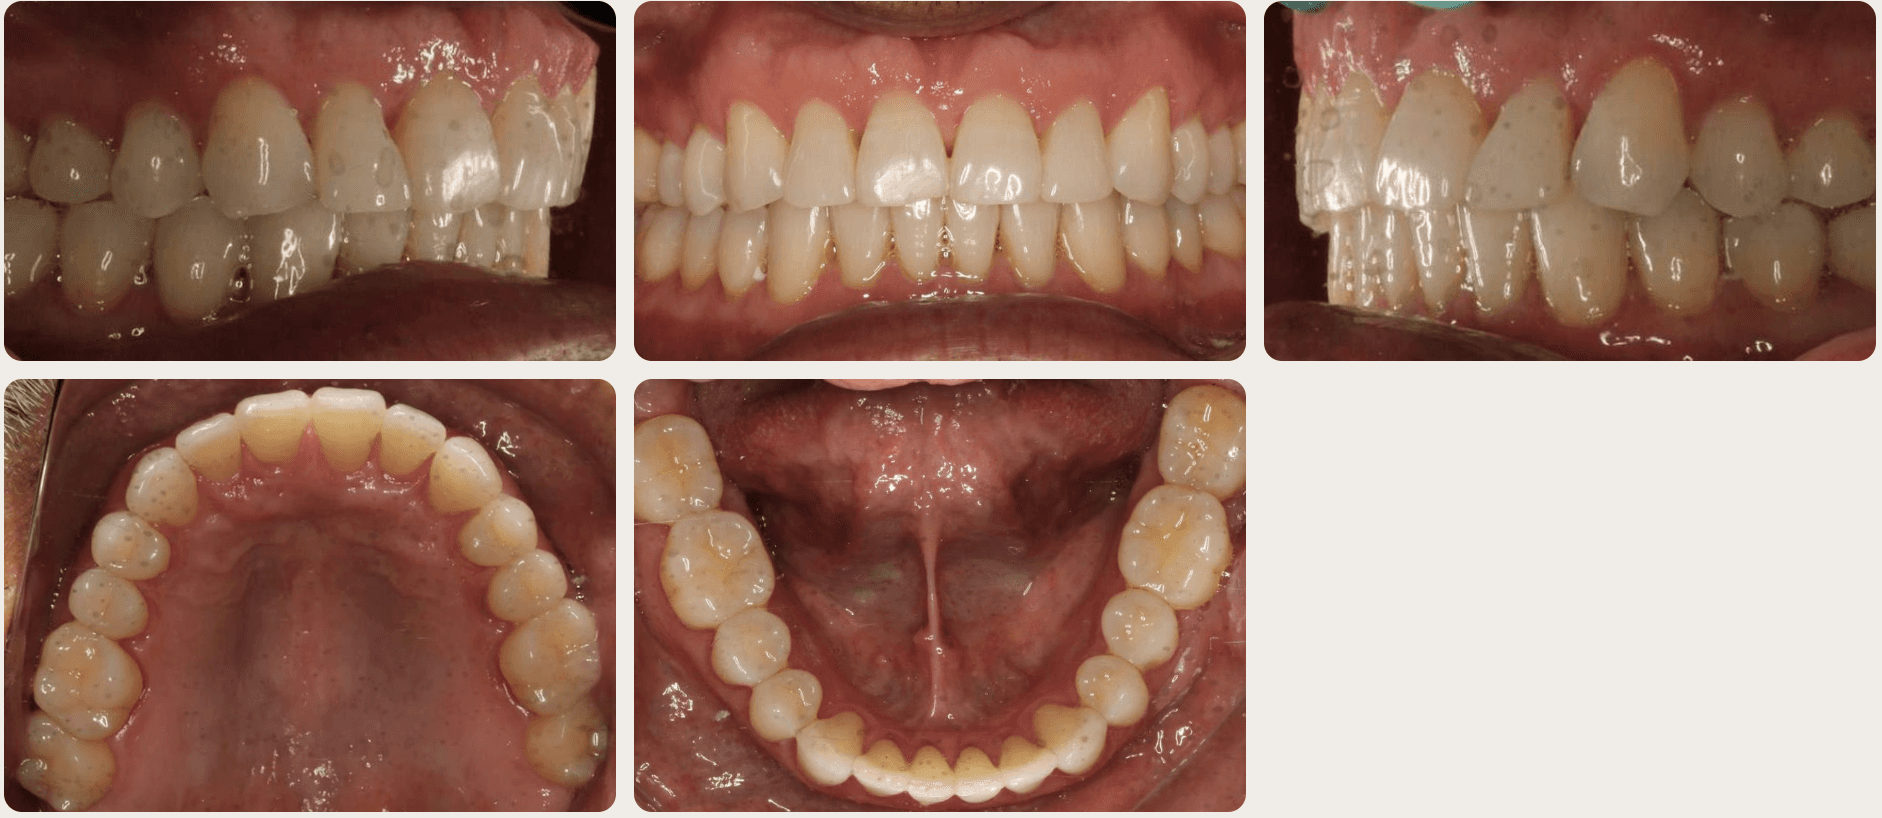

Diagnosis: A mix of crowding and mild spacing, moderate curve of Spee, black triangles, significant overjet, reverse smile display

Adjuncts: Bite ramps, attachments, IPR

Final results

INTRAORAL